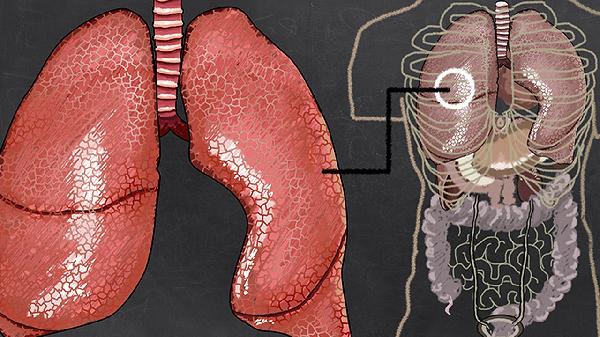

肺气肿腿疼怎么回事儿

肺气肿患者出现腿疼可能由缺氧代偿反应、肺动脉高压、右心衰竭、下肢静脉血栓、骨质疏松等原因引起,需通过氧疗、利尿剂、抗凝治疗、钙剂补充等方式干预。

肺气肿导致慢性缺氧时,机体通过增加红细胞数量提高携氧能力,血液黏稠度增高可能引发下肢微循环障碍。长期缺氧还会引起肌肉无力和代谢性酸中毒,表现为活动后腿部酸痛。需通过长期低流量吸氧改善血氧饱和度,配合有氧运动增强肌肉耐受力。

肺血管阻力增加会导致右心室负荷加重,可能引发下肢静脉回流受阻。这种情况通常伴随踝部水肿和皮肤发绀,疼痛呈胀痛感。治疗需使用利尿剂减轻水肿,必要时需应用靶向药物降低肺动脉压力。

长期肺动脉高压可能进展为肺源性心脏病,右心功能失代偿时会出现肝颈静脉回流征阳性、下肢凹陷性水肿等症状。腿部疼痛多呈对称性,与静脉淤血相关。需限制钠盐摄入,使用地高辛等强心药物改善心功能。

肺气肿患者因活动量减少、血液高凝状态易形成深静脉血栓,表现为单侧腿部突发肿胀剧痛,皮肤温度升高。需立即进行血管超声检查,确诊后需使用低分子肝素等抗凝药物,严重时需放置下腔静脉滤器。

长期使用糖皮质激素治疗肺气肿可能诱发骨质疏松,表现为负重时下肢骨骼隐痛,夜间可能加重。需进行骨密度检测,补充维生素D和钙剂,必要时使用双膦酸盐类药物抑制骨吸收。